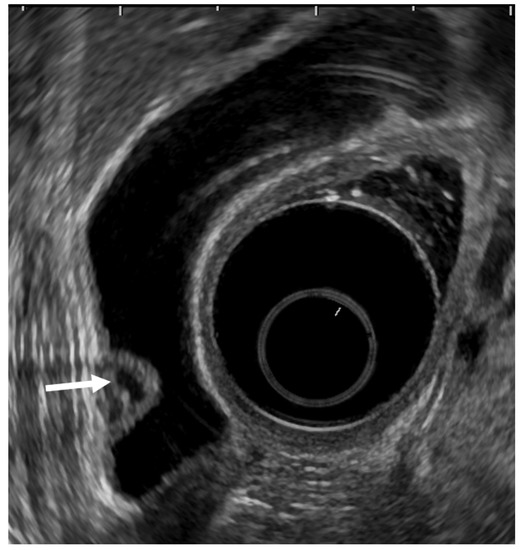

- Mizuguchi, M.; Kudo, S.; Fukahori, T.; Matsuo, Y.; Miyazaki, K.; Tokunaga, O.; Koyama, T.; Fujimoto, K. Endoscopic ultrasonography for demonstrating loss of multiple-layer pattern of the thickened gallbladder wall in the preoperative diagnosis of gallbladder cancer. Eur. Radiol. 1997, 7, 1323–1327. [Google Scholar] [CrossRef] [PubMed]

- Kim, H.J.; Park, J.H.; Park, D.I.; Cho, Y.K.; Sohn, C.I.; Jeon, W.K.; Kim, B.I.; Choi, S.H. Clinical usefulness of endoscopic ultrasonography in the differential diagnosis of gallbladder wall thickening. Dig. Dis. Sci. 2012, 57, 508–515. [Google Scholar] [CrossRef] [PubMed]

- Fujita, N.; Noda, Y.; Kobayashi, G.; Kimura, K.; Yago, A.; Mochizuki, F. Analysis of the Layer Structure of the Gallbladder Wall Delineated by Endoscopic Ultrasound Using the Pinning Method. Dig. Endosc. 1995, 7, 353–356. [Google Scholar] [CrossRef]

- Fujita, N.; Noda, Y.; Kobayashi, G.; Kimura, K.; Yago, A. Diagnosis of the depth of invasion of gallbladder carcinoma by EUS. Gastrointest. Endosc. 1999, 50, 659–663. [Google Scholar] [CrossRef]